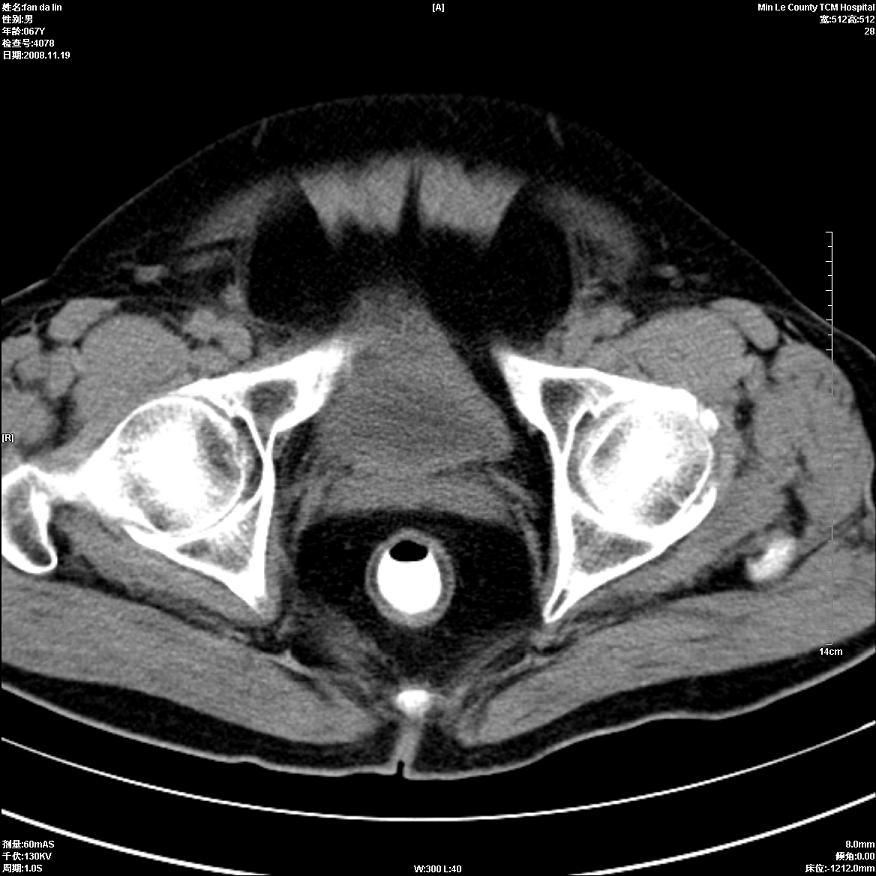

标题: CT16698:M67Y,看看直肠下端是不是病变 [打印本页]

标题: CT16698:M67Y,看看直肠下端是不是病变

粘膜皱壁,不除外内痔

直肠及乙状结肠管壁均增厚,考虑炎症.

直乙交界处肠壁不规则增厚,还是做个肠镜吧

只是肠壁局限性增厚,但难说明问题。